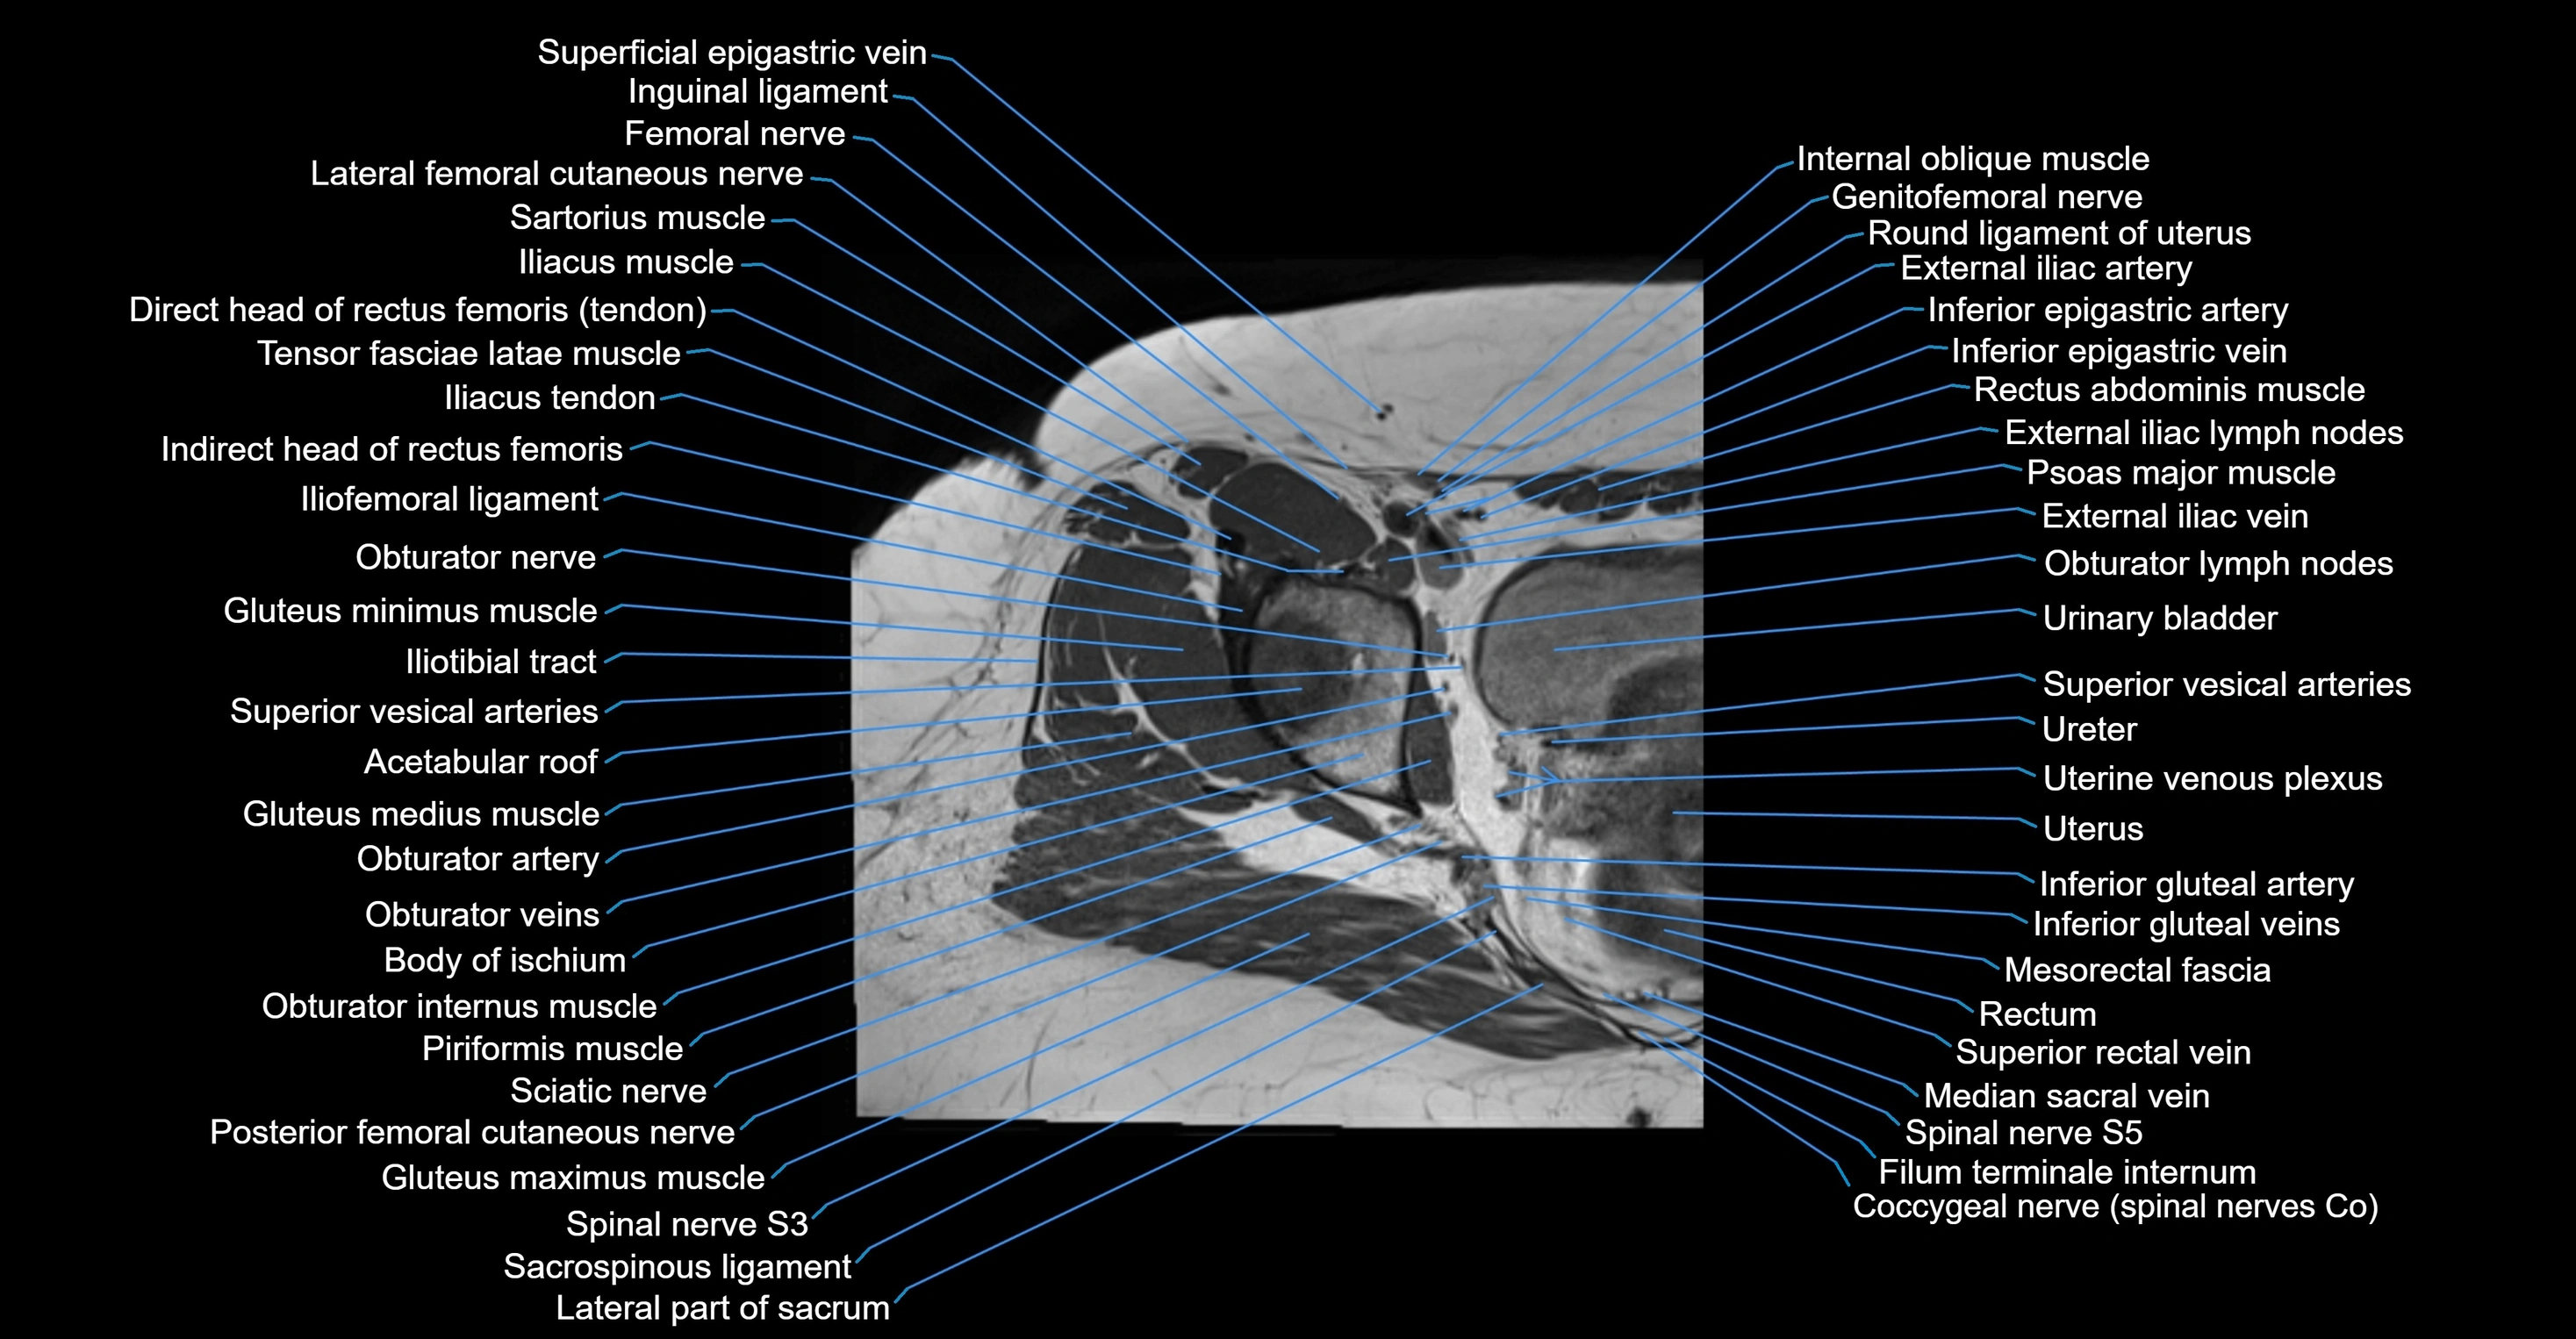

- External iliac lymph nodes

- External iliac vein

- Genitofemoral nerve

- Gluteus maximus muscle

- Gluteus medius muscle

- Gluteus minimus muscle

- Iliotibial tract

- Inferior epigastric artery

- Inferior epigastric veins

- Inguinal ligament

- Median sacral vein

- Mesorectal fascia

- Obturator internus muscle

- Obturator lymph nodes

- Obturator nerve

- Posterior femoral cutaneous nerve

- Psoas major muscle

- Rectum

- Round ligament of uterus

- Spinal nerve S5

- Superior rectal vein

- Superior vesical artery

- Tensor fasciae latae muscle

- Urinary bladder

- Uterine venous plexus

- Uterus